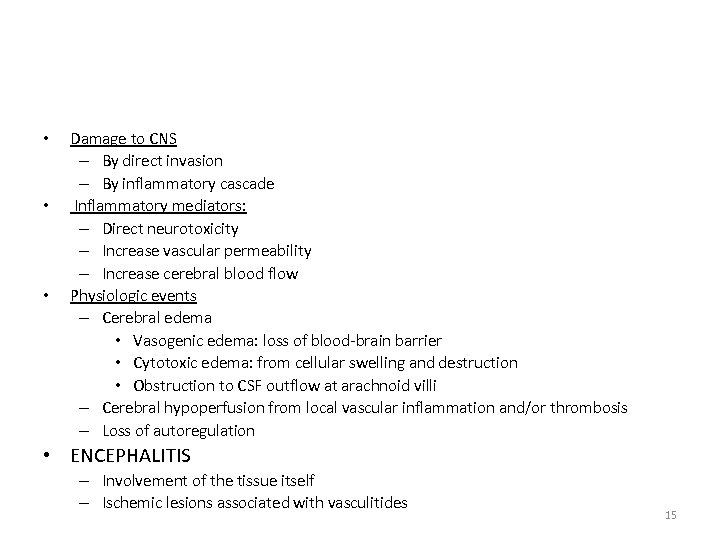

• • • Damage to CNS – By direct invasion – By inflammatory cascade Inflammatory mediators: – Direct neurotoxicity – Increase vascular permeability – Increase cerebral blood flow Physiologic events – Cerebral edema • Vasogenic edema: loss of blood-brain barrier • Cytotoxic edema: from cellular swelling and destruction • Obstruction to CSF outflow at arachnoid villi – Cerebral hypoperfusion from local vascular inflammation and/or thrombosis – Loss of autoregulation • ENCEPHALITIS – Involvement of the tissue itself – Ischemic lesions associated with vasculitides 15